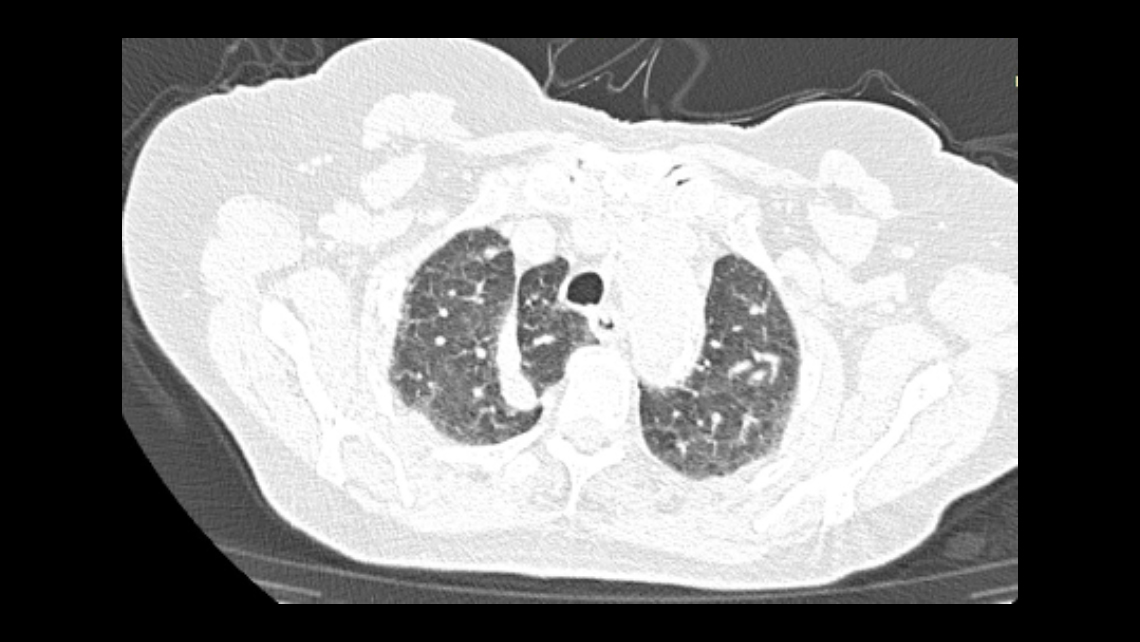

Paciente femenina de 85 años de edad con diagnostico ecográfico de aterosclerosis del sistema arterial del miembro inferior izquierdo y trombosis arterial a nivel femoro-popliteo; además con antecedente de neumopatia viral por COVID-19, razón por la cual acude al centro de diagnóstico para realizar estudio angiotomográfico de miembros inferiores y de tórax respectivamente.

Se observan en el estudio tomográfico de tórax hallazgos radiológicos compatibles con neumopatia viral por COVID-19, cardiomegalia y además se evidencia; lóbulo y cisura accesoria en el LSD, en relación a cisura y lóbulo accesorio de la vena ácigos.